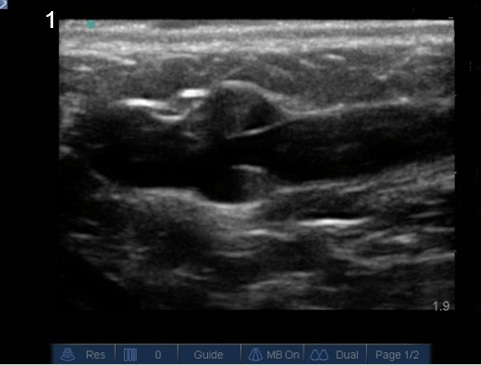

Gain Ideal Image